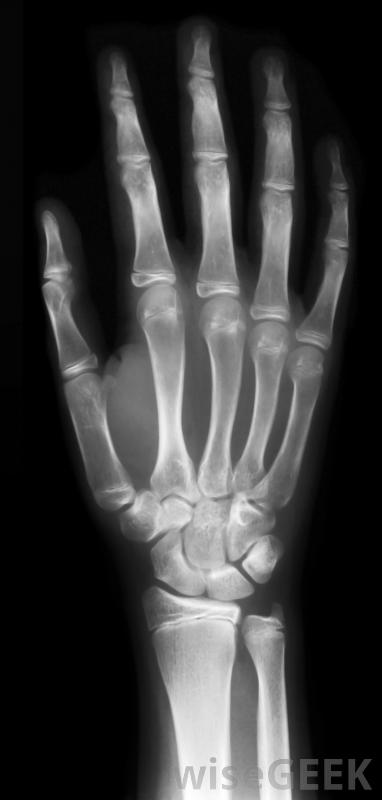

X光可以在紧急护理机构进行通常情况下,这种类型的护理是在独立于医院的诊所中提供的,其理念是,当门诊患者无法预约常规医生,且病情不严重,不值得进行紧急护理时,他们可以前往紧急护理机构去急诊室。紧急护理医生充当普通医生的替身,而该机构通过处理非急诊病例来减轻急诊室的负担

紧急护理设施可以通过接收无生命危险疾病的患者来减轻急诊室的负担,这些类型的护理设施在20世纪70年代开始激增许多健康保险公司强烈鼓励他们的客户尽可能使用紧急护理,因为这样可以降低成本,并确保在达到紧急医疗级别之前就得到治疗。例如,在24小时内治疗喉咙痛是非常容易控制的,但如果忽视它,它可能会成为一个紧急医疗事件。通过提供这种级别的医疗服务,医生可以迅速干预。一些医疗机构接受不定期访问,虽然在医疗机构人满为患的时候可能会有短暂的等待。其他人要求人们预约,但他们保证在24小时内预约。任何试图在24小时内预约医生的人都知道,能在一天内就诊会带来很大的不同。根据医疗机构的水平,这些诊所可能会提供各种各样的服务。在需要的时候,如果情况比原先想象的更严重,该设施可以将患者转诊到医院进行紧急护理。该设施还可以在实验室进行基本的医学测试,还可以包括一些医疗成像设备,如x射线和超声波,以用于诊断病人在急症治疗后,可建议他或她到正规医生或全科医生进行随访。如果病人的病例需要特殊技能,该机构可能会提供转介给一名专家,该专家将负责后续护理。